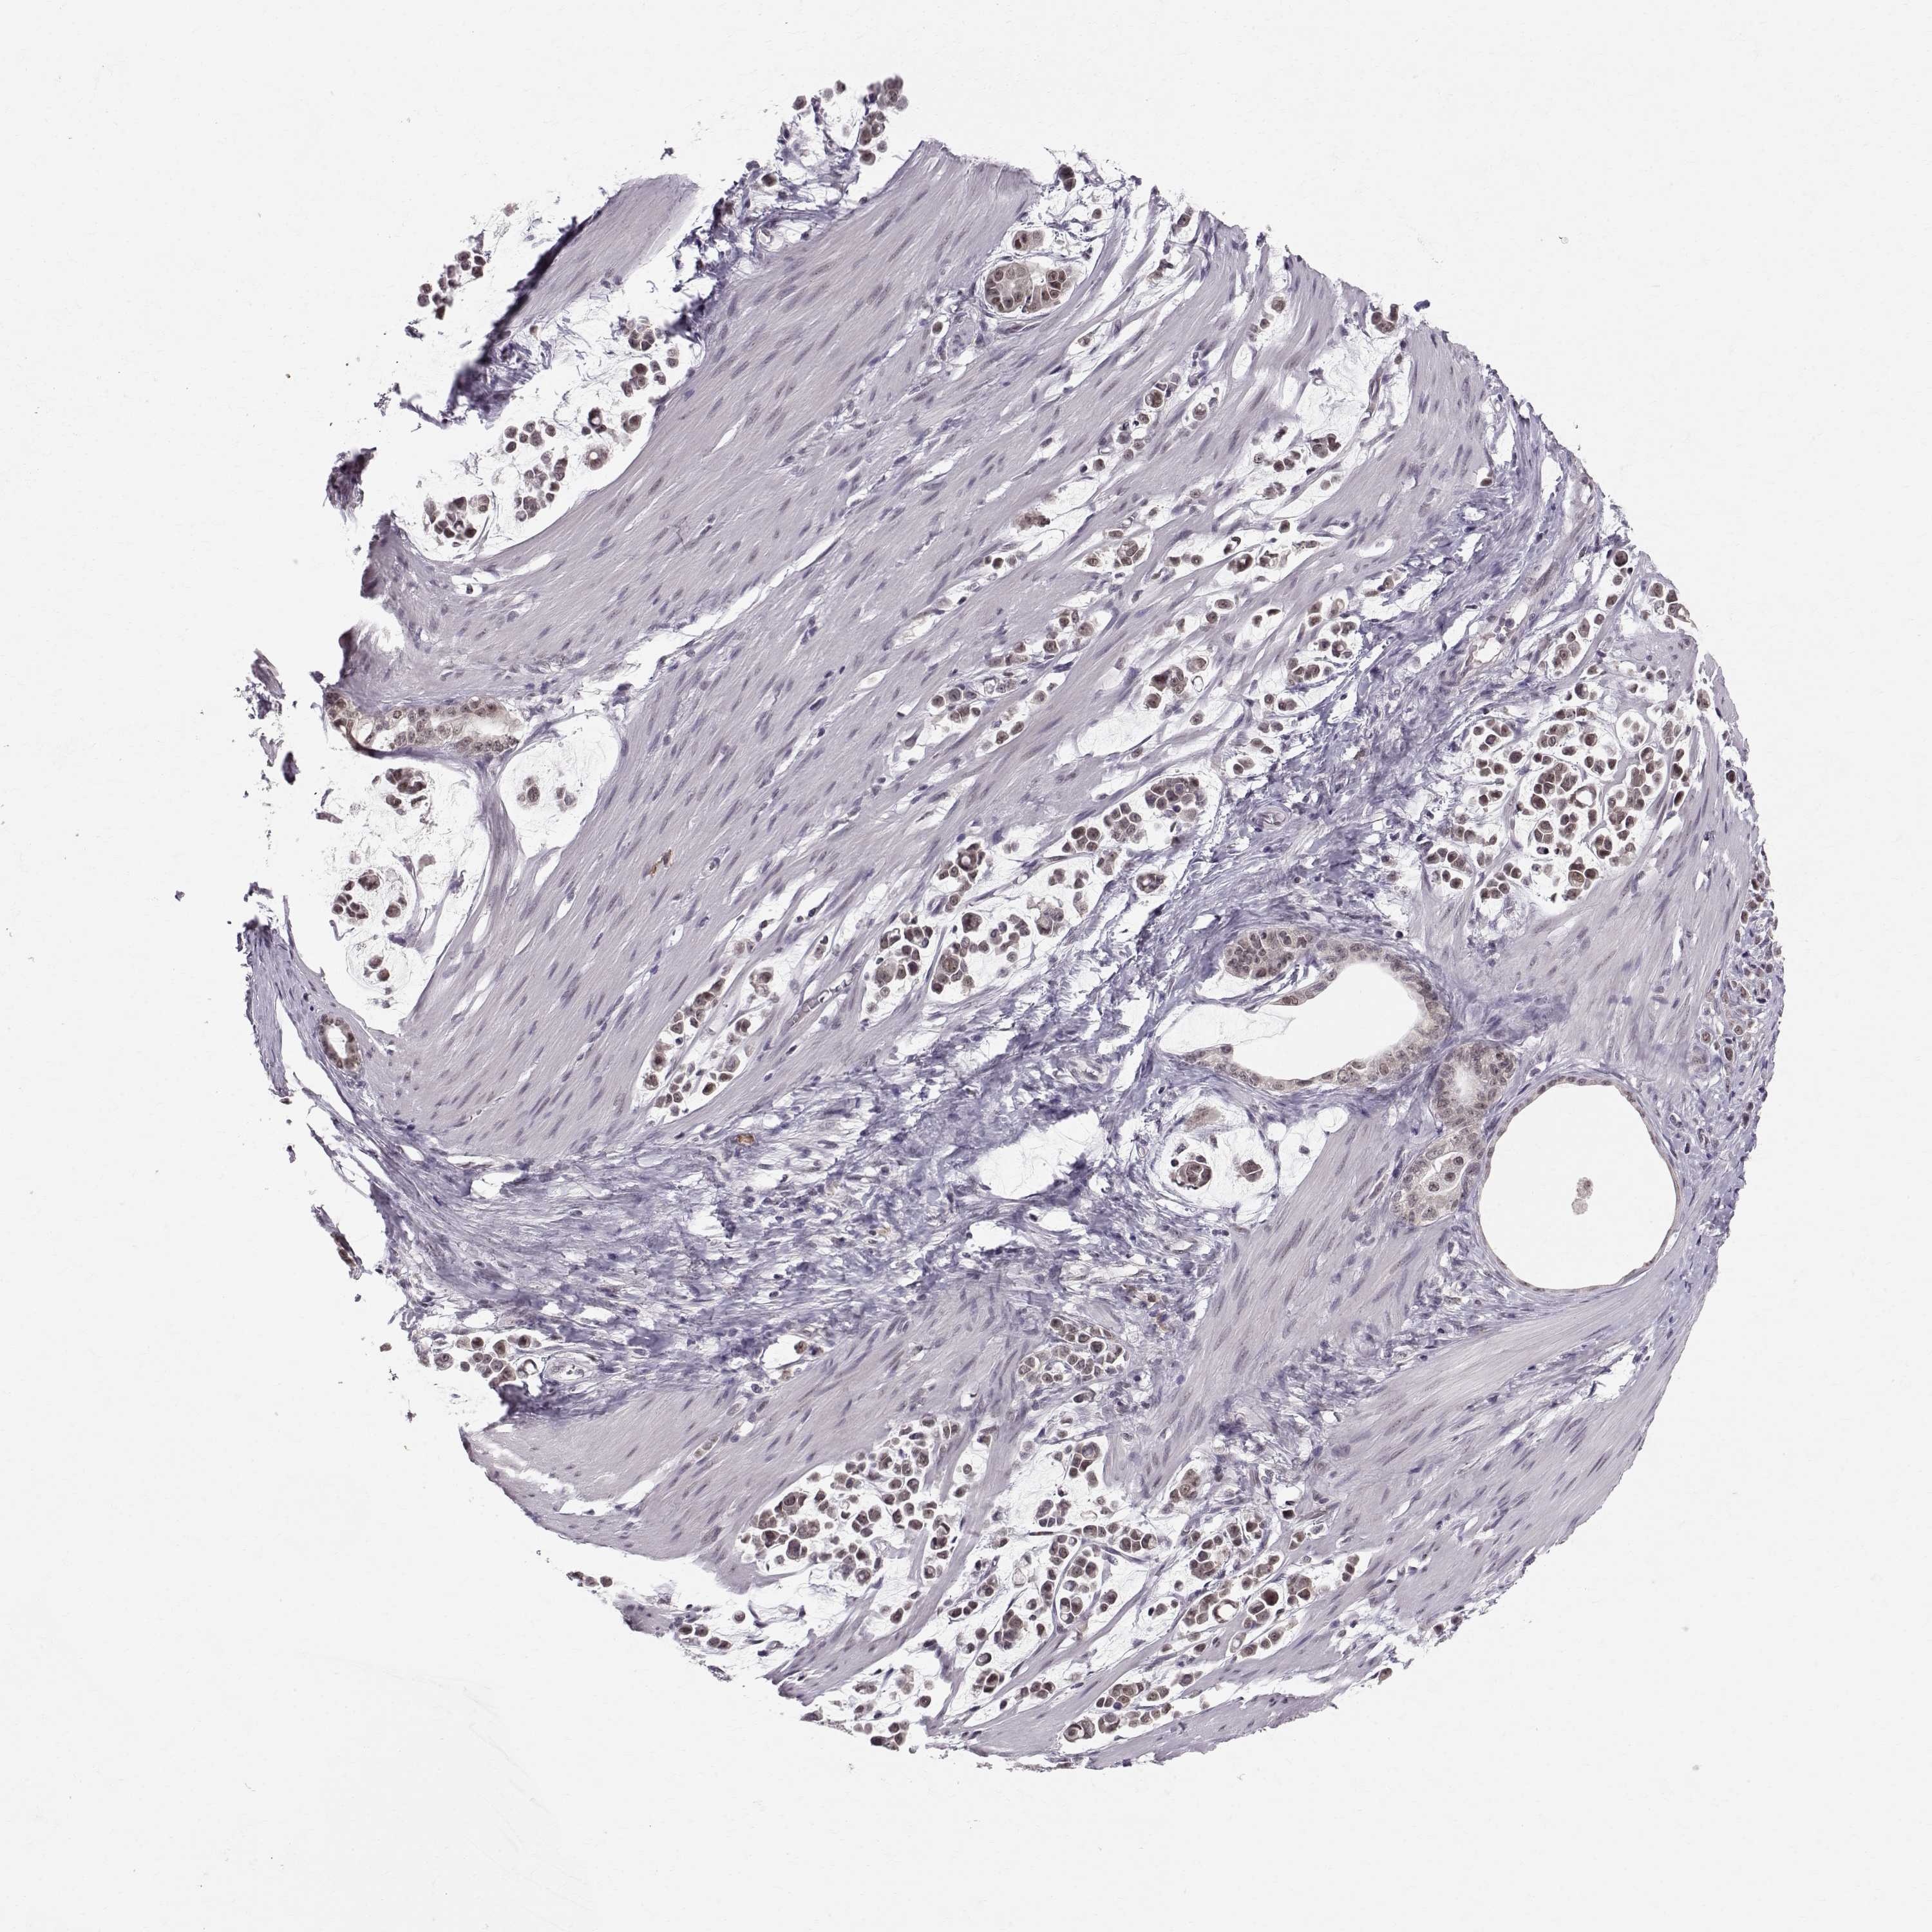

STOMACH CANCER - Protein expressioni

A mouse-over function shows sample information and annotation data. Click on an image to view it in a full screen mode. Samples can be filtered based on level of antibody staining by selecting one or several of the following categories: high, medium, low and not detected. The assay and annotation is described here.

Note that samples used for immunohistochemistry by the Human Protein Atlas do not correspond to samples in the TCGA dataset.

Antibody stainingi

Antibody staining in the annotated cell types in the current human tissue is reported as not detected, low, medium, or high, based on conventional immunohistochemistry profiling in selected tissues. This score is based on the combination of the staining intensity and fraction of stained cells.

Each image is clickable and will lead to virtual microscopy that enables deeper exploration of all samples and also displays staining intensity scores, fraction scores and subcellular localization as well as patient and tissue information for each sample.

Antibody HPA050398

Staining

High

Medium

Low

Not detected

Intensity

Strong

Moderate

Weak

Negative

Quantity

>75%

75%-25%

<25%

None

Location

Nuclear

Cytoplasmic/membranous

Cytoplasmic/membranous,nuclear

Adenocarcinoma, NOS

Adenocarcinoma, High grade